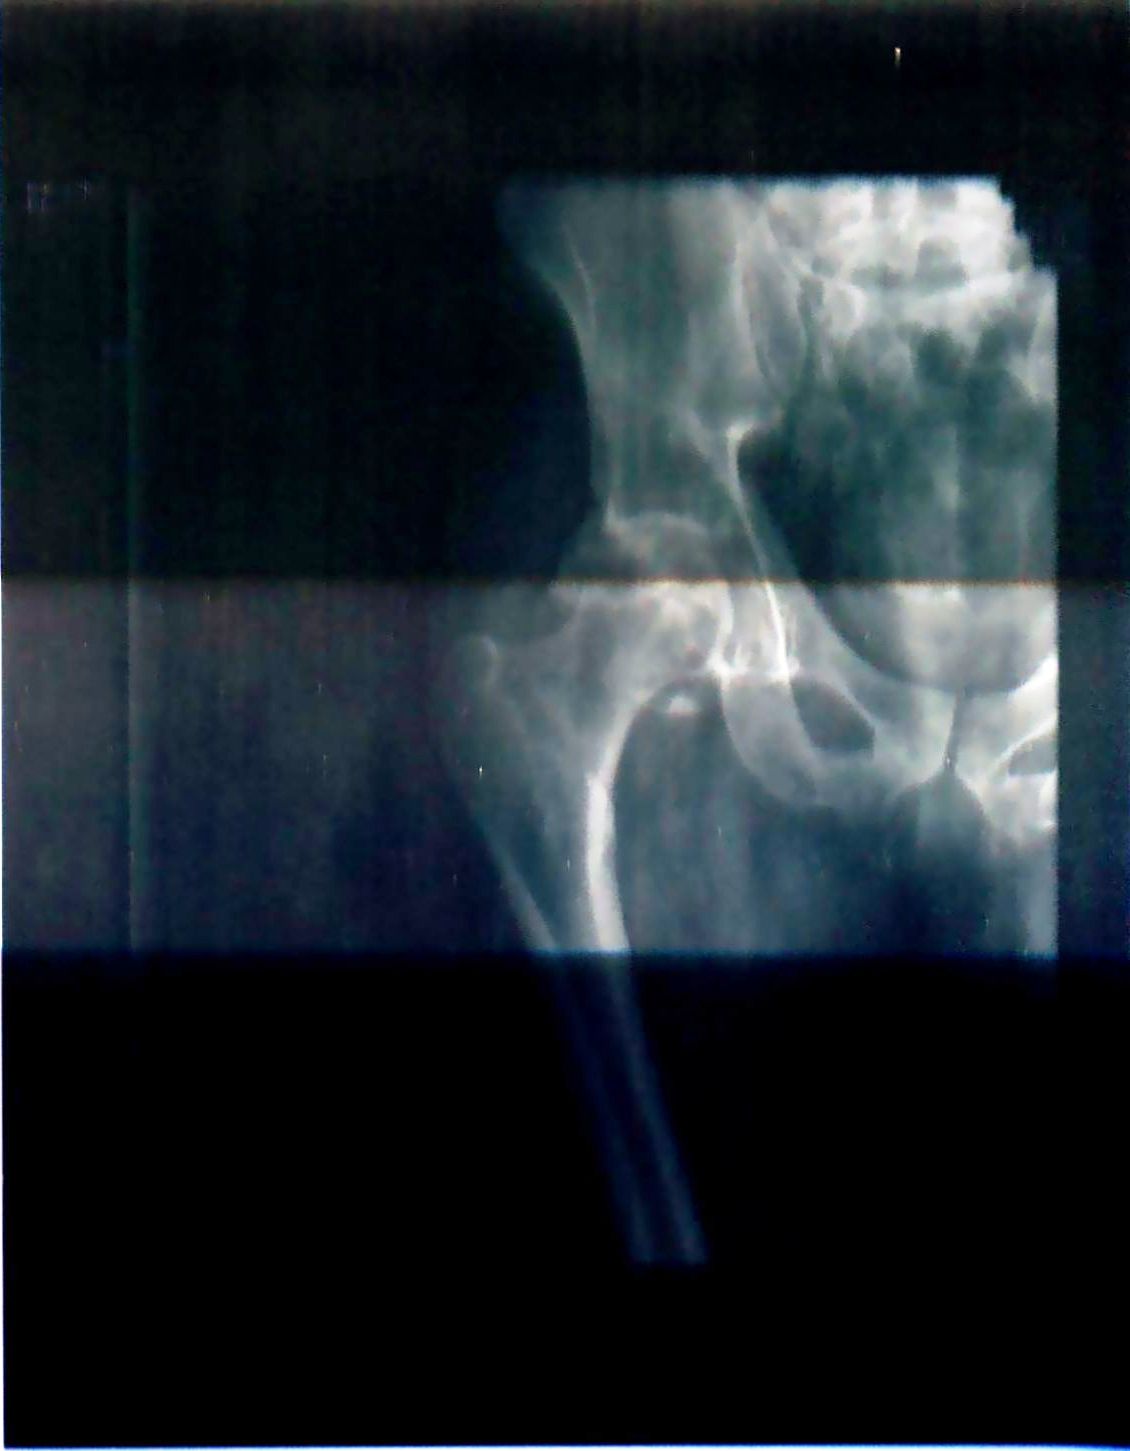

Травма 3 года назад,перелом верт.впадины,перелом сед.костей,компрес.перелом L1

Прошло 3 год,все переломы консолидированы,но осталась проблема с левым тазоб.суставом,движ.сустава свободные,переодические боли.Консульт.в разных клиниках,в одних консерват.лечение,в других эндопрот.Помогите разобраться.Спасибо.

• Кликните для загрузки файла ренген 002.jpg

86KB (88737 bytes)

Разобраться по единичной рентгенограмме плохого качества не получится. Рентгенограммы (хорошо сфотографированные, не такую муть) надо представить еще в крестцово-вертлужной и запирательной проекциях. А также необходимы данные компьютерной томографии. Если есть возможность, со всем этим появитесь на очную консультацию в клинику травматологии УНИИТО. Тед. (343)371-31-82.